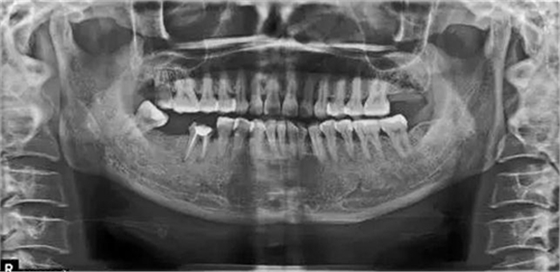

病例2:T女士,42歲。左上后牙缺失3年。就診要求恢復咀嚼功能。

X片上可見T女士左上后牙缺失。根據(jù)患者口內和全身狀況。制定計劃為:右上后牙種植修復。